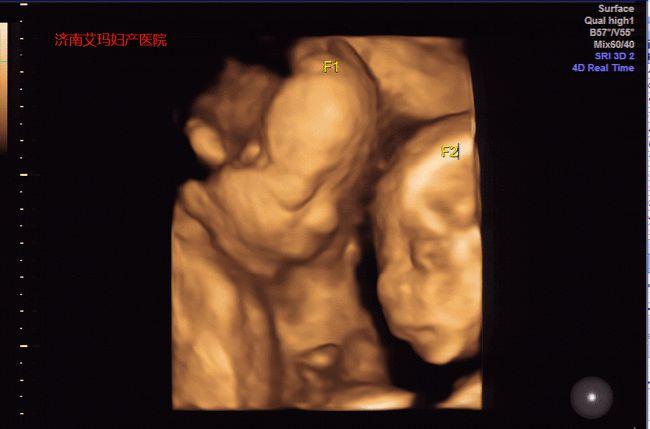

四个月龙凤胎彩超图片

四个月龙凤胎彩超图片,四个月双胞胎彩超图片

树下 同龄 2020年10月同龄圈 这个双胞胎四维彩超像男孩女孩.

龙凤胎的四维彩超图片

四个月龙凤胎b超图片